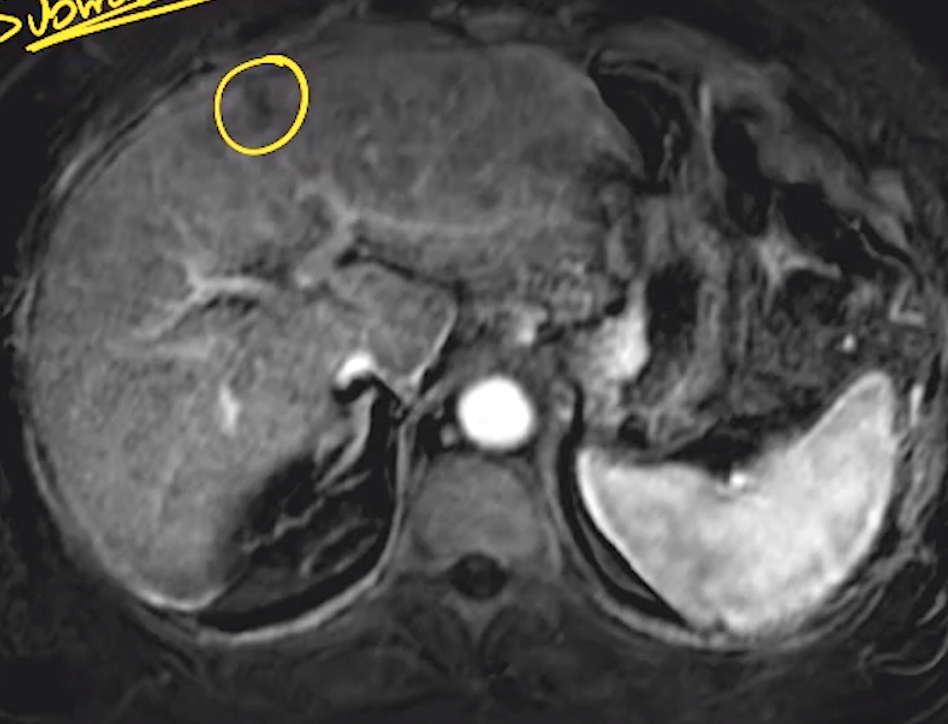

Hemangioma

• Disorganized mass of blood vessels ultimately supplied by the hepatic artery

• Commonly peripheral in liver

• T1: hypointense (relative to liver parenchyma)

• T2: hyperintense (relative to liver parenchyma)

• T1 C +: peripheral nodular discontinuous enhancement with centripetally filling

• Retain contrast on delayed sequences